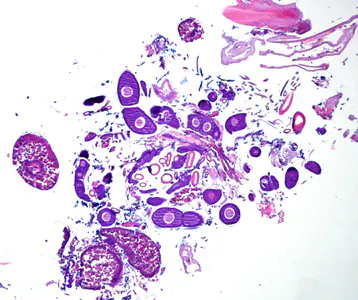

Case #275 – May, 2010

A 70-year-old female, who had recently returned from a trip to Madagascar, went to the hospital for a painful sensation on the underside of her left foot while walking. Examination of the area between the hallux and index toes revealed an ulcerative lesion. A biopsy was performed and sent to the Pathology Department for work-up. The specimen was sectioned, stained with hematoxylin and eosin (H&E) and examined by the attending pathologist. Figures A and B show what was observed at 40x magnification. Figures C and D show the same fields at 200x magnification, respectively. What is your diagnosis? Based on what criteria?

Figure A